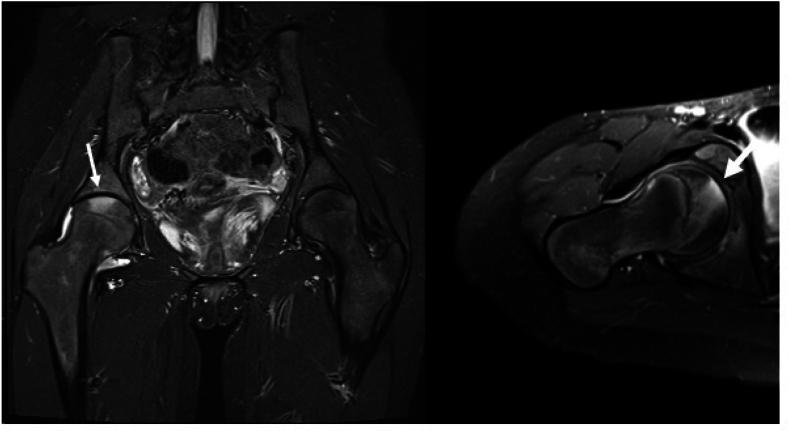

Idiopathic chondrolysis of the hip (ICH) is a rare condition characterized by the acute and rapidly progressive destruction of cartilage. ICH typically presents in peri-pubescent females with acutely worsening hip pain, a deterioration in range of motion (ROM), and distinctive imaging and biopsy findings. Variability in outcomes, ranging from complete resolution of symptoms to a permanently ankylosed hip, has been observed in both conservatively and aggressively treated cases. The treatments described often consider patient factors and disease stage yet consist of inconsistent combinations of pharmacologic and surgical approaches. Consequently, it is challenging to compare outcomes across different treatment methods. Although recent literature has enhanced our understanding of the epidemiology and natural history of ICH, a consensus on optimal management is still lacking, highlighting the need to investigate the components and outcomes of evolving treatments. Since the last systematic review of imaging findings and treatment regimens for ICH, over 50 new cases have been documented in the literature. However, limited data still exist regarding patient-reported outcomes. Our aim is to review and contribute to the current evidence guiding the management of ICH by analyzing data on presentation, clinical and radiologic findings, and treatment outcomes.